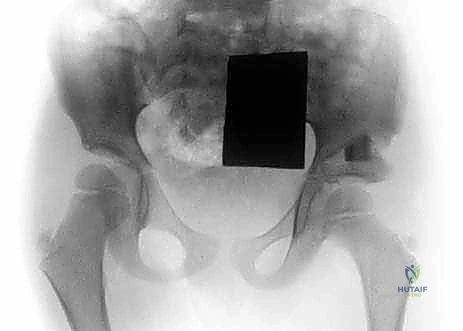

- تشوه مفصل الورك (Hip Dysplasia): عدم اكتمال نمو الحق (Acetabulum) ورأس عظمة الفخذ.

- الفخذ الأفحج (Coxa Vara): نقصان حاد في الزاوية بين عنق وجسم عظمة الفخذ، مما يؤدي إلى ضعف شديد في العضلات المبعدة للورك وعرج ملحوظ.

يعتمد الأستاذ الدكتور محمد هطيف على التصنيفات العالمية الحديثة (مثل تصنيف Paley) لتقييم كل حالة بدقة متناهية. ينقسم التصنيف بناءً على سلامة مفصل الورك والركبة، ومقدار القصر المتوقع عند البلوغ. هذا التقييم الإشعاعي والسريري الدقيق هو حجر الأساس الذي تُبنى عليه خطة العلاج طويلة الأمد.

2. قطع عظم ديجا (Dega Osteotomy)

في الحالات التي يكون فيها الحق (تويج الحوض) ضحلاً ولا يغطي رأس الفخذ بشكل كافٍ (Hip Dysplasia)، يجري الدكتور هطيف عملية "ديجا". يتم فيها عمل شق في عظام الحوض وثنيه للأسفل لتكوين سقف متين يغطي رأس الفخذ، ثم يتم وضع طعم عظمي لتثبيت الوضع الجديد. هذا الإجراء ضروري لمنع خلع الورك أثناء عملية التطويل اللاحقة.